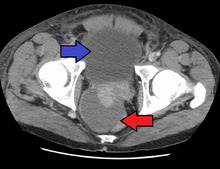

Abscess of the prostate (red arrow) resulting in urinary retention (blue arrow)

Acute prostatitis is relatively easy to diagnose due to its symptoms that suggest infection. The organism may be found in blood or urine, and sometimes in both.[2] Common bacteria are Escherichia coli, Klebsiella, Proteus, Pseudomonas, Enterobacter, Enterococcus, Serratia, and Staphylococcus aureus. This can be a medical emergency in some patients and hospitalization with intravenous antibiotics may be required. A complete blood count reveals increased white blood cells. Sepsis from prostatitis is very rare, but may occur in immunocompromised patients; high fever and malaise generally prompt blood cultures, which are often positive in sepsis. A prostate massage should never be done in a patient with suspected acute prostatitis, since it may induce sepsis. Since bacteria causing the prostatitis is easily recoverable from the urine, prostate massage is not required to make the diagnosis. Rectal palpation usually reveals an enlarged, exquisitely tender, swollen prostate gland, which is firm, warm, and, occasionally, irregular to the touch. C-reactive protein is elevated in most cases.[4]

Severely ill patients may need hospitalization, while nontoxic patients can be treated at home with bed rest, analgesics, stool softeners, and hydration. Men with acute prostatitis complicated by urinary retention are best managed with a suprapubic catheter or intermittent catheterization. Lack of clinical response to antibiotics should raise the suspicion of an abscess and prompt an imaging study such as a transrectal ultrasound (TRUS).[7]